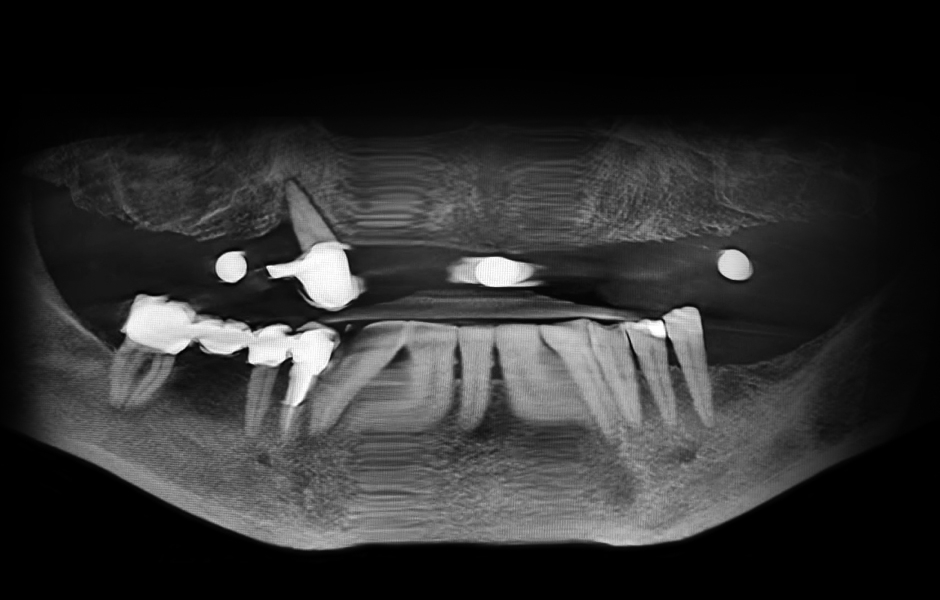

Obr. 1: Klinická a radiologická výchozí situace v horní čelisti se selhávajícími předchozími rekonstrukcemi.

Obr. 2: Klinická a radiologická výchozí situace v horní čelisti se selhávajícími předchozími rekonstrukcemi.

Obr. 3: Klinická a radiologická výchozí situace v horní čelisti se selhávajícími předchozími rekonstrukcemi.

Obr. 4: Klinická a radiologická výchozí situace v horní čelisti se selhávajícími předchozími rekonstrukcemi.

3D zobrazovací vyšetření potvrdilo, že kostní situace v maxile je vhodná pro plánovaný koncept SKY Fast&Fixed se šesti implantáty – dvěma rovnými implantáty v předním úseku a dvěma mírně angulovanými implantáty na každé straně v distálním úseku. Snímky dále ukázaly intaktní vestibulární kostní lamely, což umožnilo po extrakci zubu 13 provést plně navigovanou implantaci. Definitivní protetická rekonstrukce byla plánována jako vysoce kvalitní kompozitní náhrada na podkladě digitálně vytvořeného idealizovaného setupu pro provizorní rekonstrukci (obr. 5–8).